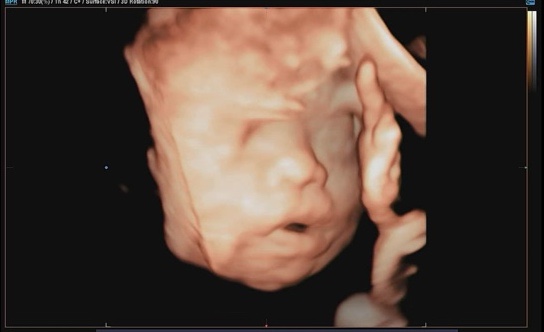

임신일기 :: 임신 28주, 29주 / 임신 8개월, 배뭉침, 임산부의 날, 세브란스 분만실 방문

임신일기 :: 임신 26주, 27주 / 싸이벡스 바구니 카시트, 트립트랩 글레시어 그린, 입체초음파, 임신부 감기

임신 26주 땡큐와 베리 26주 입성 ? 이전까지는 그래도 컨디션이 꽤 좋았는데 26주 좀 지나고 나니까 배...